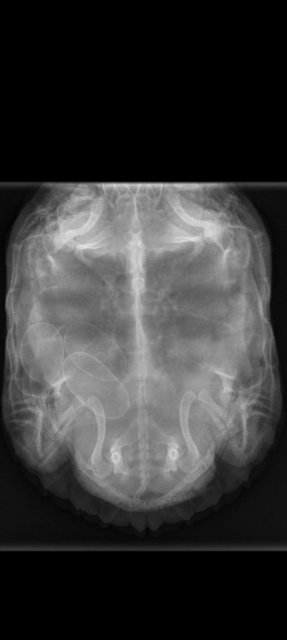

9.В ветклинике делали только рентген. Препараты не вводил.

В последнее время черепаха себя очень беспокойно ведёт, стала спать на островке, мало времени проводит в воде, перестала есть в контейнере, хорошо хоть в аквариуме поела. Не знал, что с ней, почитал форум. Предположительно беременность. Выпустил сегодня на пол, она начала рыть задними лапами, повезли на рентген. Как я понял это и есть яйцо. Хочу услышать совет от профессионалов. Что делать и как помочь черепахе?

Screenshot_2024-01-14-18-46-46-49_68e74cc0265513bba3f4cf8e2c9891fe.jpg